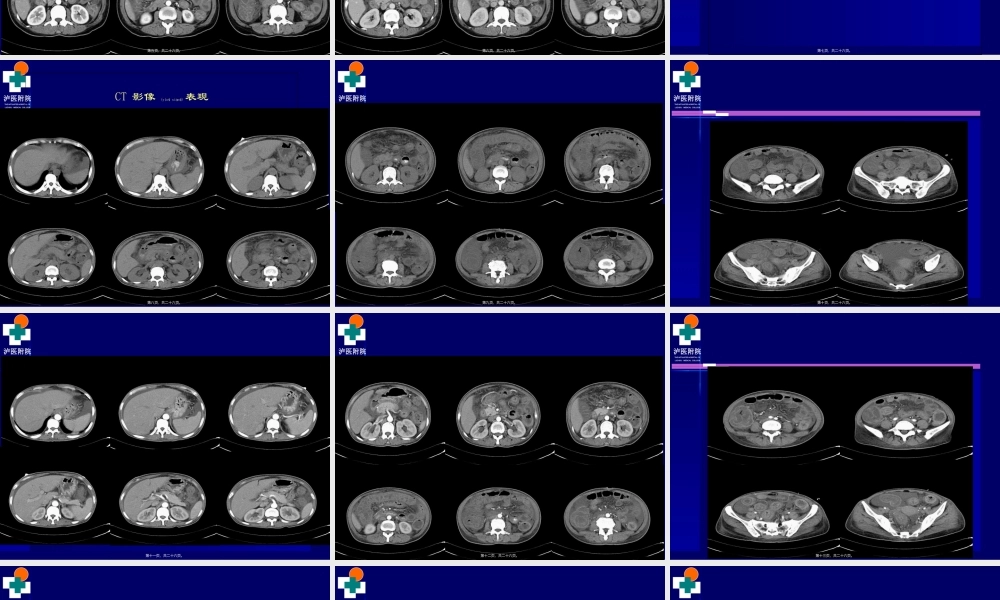

泸医附院THEAFFILIATEDHOSPITALOFLUZHOUMEDICALCOLLEGE病例病例(bìnglì)(bìnglì)11病史资料病史资料女女4646岁岁临床表现:临床表现:1+1+月,患者因月,患者因""肠梗阻肠梗阻""在我院普一科住院治疗,肛门排气排便后出院,出院后患者一直在我院普一科住院治疗,肛门排气排便后出院,出院后患者一直(yīzhí)(yīzhí)感腹胀,感腹胀,10+10+天前开始出现腹泻,伴恶心,呕吐。每日腹泻约天前开始出现腹泻,伴恶心,呕吐。每日腹泻约1010次,呕吐频繁,呕吐次,呕吐频繁,呕吐物为胃内容物,无黏液,脓血,物为胃内容物,无黏液,脓血,入院诊断:入院诊断:11、腹泻原因待查?、腹泻原因待查?11)、慢性胰腺炎?)、慢性胰腺炎?22)、感染性腹泻)、感染性腹泻?3?3)、药)、药物性腹泻?物性腹泻?22、水电解质紊乱、水电解质紊乱11)、严重低钾血症)、严重低钾血症,,22)、代谢性酸中毒)、代谢性酸中毒;;33、、胃潴留胃潴留..第一页,共二十六页。泸医附院THEAFFILIATEDHOSPITALOFLUZHOUMEDICALCOLLEGE院外电解质K+2.06mmol/L胃镜提示:慢性非萎缩性胃炎(wèiyán)伴胆汁反流,胃潴留,动脉血气分析K+<2.0mmol/L,BE-8mmol/L第二页,共二十六页。泸医附院THEAFFILIATEDHOSPITALOFLUZHOUMEDICALCOLLEGE2013/7/19我院腹部CT平扫+增强提示:1、胃壁及所扫肠道壁明显增厚、水肿,以结肠及空肠明显,肠系膜水肿,腹腔积液。2、肝脏多发小囊肿(nángzhǒng)。脾脏内局限性低密度影,小囊肿(nángzhǒng)?3、目前未见胰腺炎征象。4、胆囊切除。肝内胆管轻度扩张。第三页,共二十六页。泸医附院THEAFFILIATEDHOSPITALOFLUZHOUMEDICALCOLLEGECT平扫第四页,共二十六页。泸医附院THEAFFILIATEDHOSPITALOFLUZHOUMEDICALCOLLEGE动脉(dòngmài)期第五页,共二十六页。泸医附院THEAFFILIATEDHOSPITALOFLUZHOUMEDICALCOLLEGE静脉(jìngmài)期第六页,共二十六页。泸医附院THEAFFILIATEDHOSPITALOFLUZHOUMEDICALCOLLEGE2626//8/20138/2013我院我院CTCT多期增强多期增强(zēngqiáng)(zēngqiáng)扫描扫描第七页,共二十六页。泸医附院THEAFFILIATEDHOSPITALOFLUZHOUMEDICALCOLLEGECT影像(yǐnɡxiànɡ)表现第八页,共二十六页。泸医附院THEAFFILIATEDHOSPITALOFLUZHOUMEDICALCOLLEGE第九页,共二十六页。泸医附院THEAFFILIATEDHOSPITALOFLUZHOUMEDICALCOLLEGE第十页,共二十六页。泸医附院THEAFFILIATEDHOSPITALOFLUZHOUM...